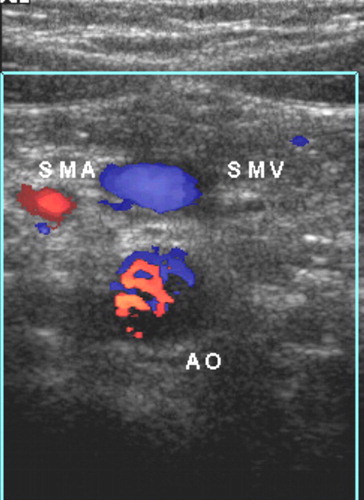

SMA/SMV Relationship

The SMV normally lies to the right of the SMA (evaluate relative to the SMA–aorta axis — draw a line through the SMA and aorta; SMV should be on the right of this line).

| SMV right of SMA | Normal — but present in 29% of malrotation cases (insufficient to exclude) |

| SMV left of SMA | Abnormal — seen in 47% of malrotation cases |

| SMV aligned with SMA | Indeterminate — seen in 24% of malrotation cases |

SMA/SMV relationship alone is unreliable. It is normal in nearly a third of malrotation cases. The more sensitive and specific sign is the position of the third part of the duodenum (D3).